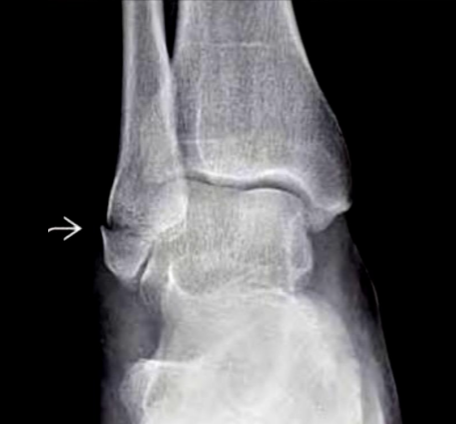

25

Weber B y C Seguna bimaleolar

Weber A: fx perone por debajo del plafón tibial B: fx perone a nivel del plafon tibial C: fx perone por encima del plafón tibial